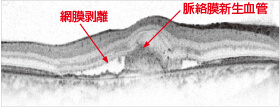

網膜断層検査(光干渉断層計)

光干渉断層計によって、眼底組織の断面の状態を調べる検査です。

滲出型の場合は、網膜剥離、網膜のむくみ、新生血管などが認められます。

正常な眼の横班像

滲出型加齢黄斑変性の黄斑像